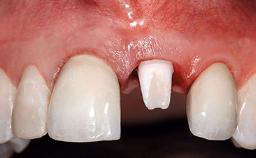

A 32-year-old female Caucasian patient with a compromised maxillary right central incisor was referred to us by a general dentist. Her chief complaints were discomfort and mobility of tooth 11 with unsatisfactory esthetics due to discoloration. The patient reported a previous trauma, some years earlier, as the origin of pathology on the afflicted tooth. Anamnesis was negative for any other dental or periodontal pathology in the remaining dentition. The patient did not take any medication and reported to be a light smoker (5–10 cigs/day). She had high esthetic expectations of her treatment. The extraoral examination revealed a high smile line with full exposure of her maxillary teeth and surrounding soft tissue in the area between the second premolars.

Lip Line No exposure of papillae Exposure of papillae Full exposure of mucosa margin

Soft Tissue Anatomy Intact Defective